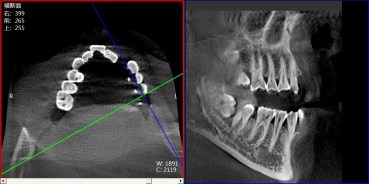

Great Quality ImagesAdopt 3D reconstruction algorithm. |